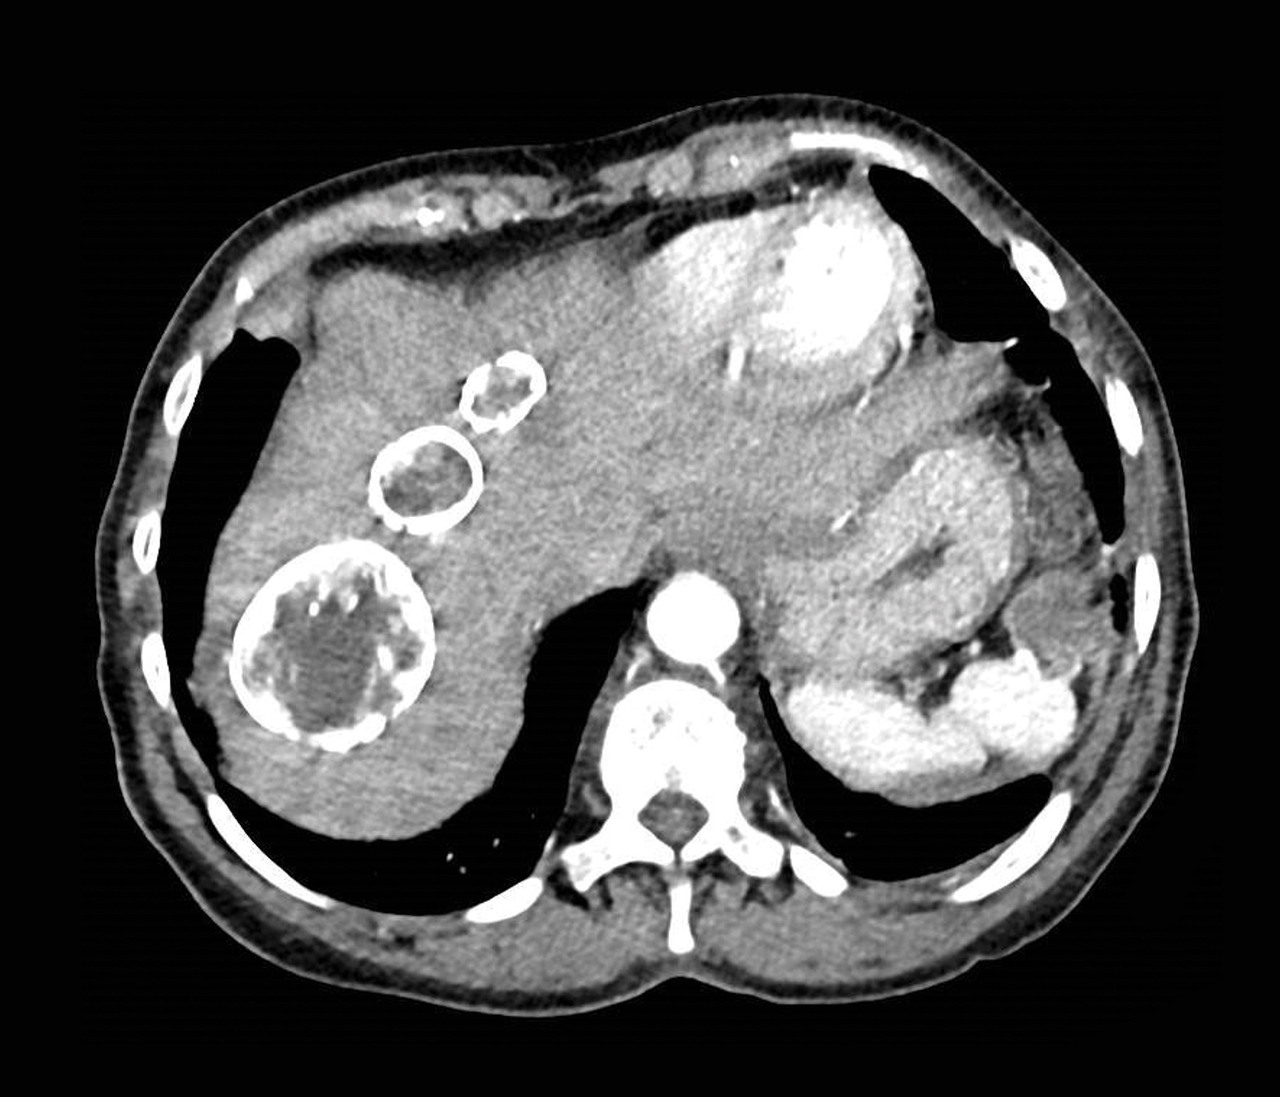

Femme de 49 ans hospitalisée pour l’exploration d’une cholestase. Quel est votre diagnostic ? A. Tuberculose B. Hydatidose C. Lymphome D. Angiomes hépatiques E. Cholangiocarcinome OK Valider mes réponses